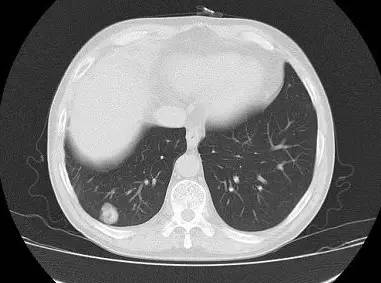

男,52岁,查体发现肺部病变

[影像描述]

右肺下叶结节样病变,内有钙化、脂肪成分,增强后可见轻度强化。

[检查结果]

右肺下叶错构瘤.

右肺下叶病变内有钙化、脂肪成分,典型爆米花样钙化,增强后可见轻度强化。